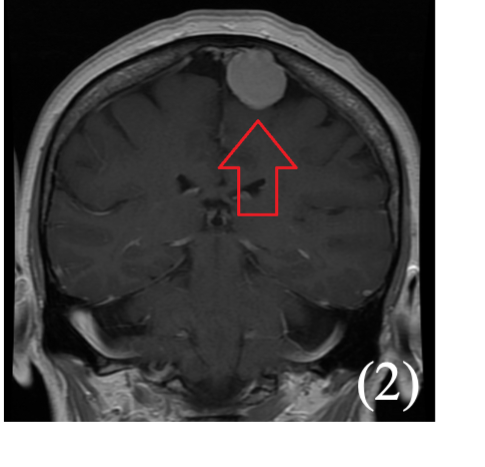

It usually arises in the cerebral hemispheres near the corpus collosum.

CT/MRI shows a classic “butterfly lesion” across the corpus callosum